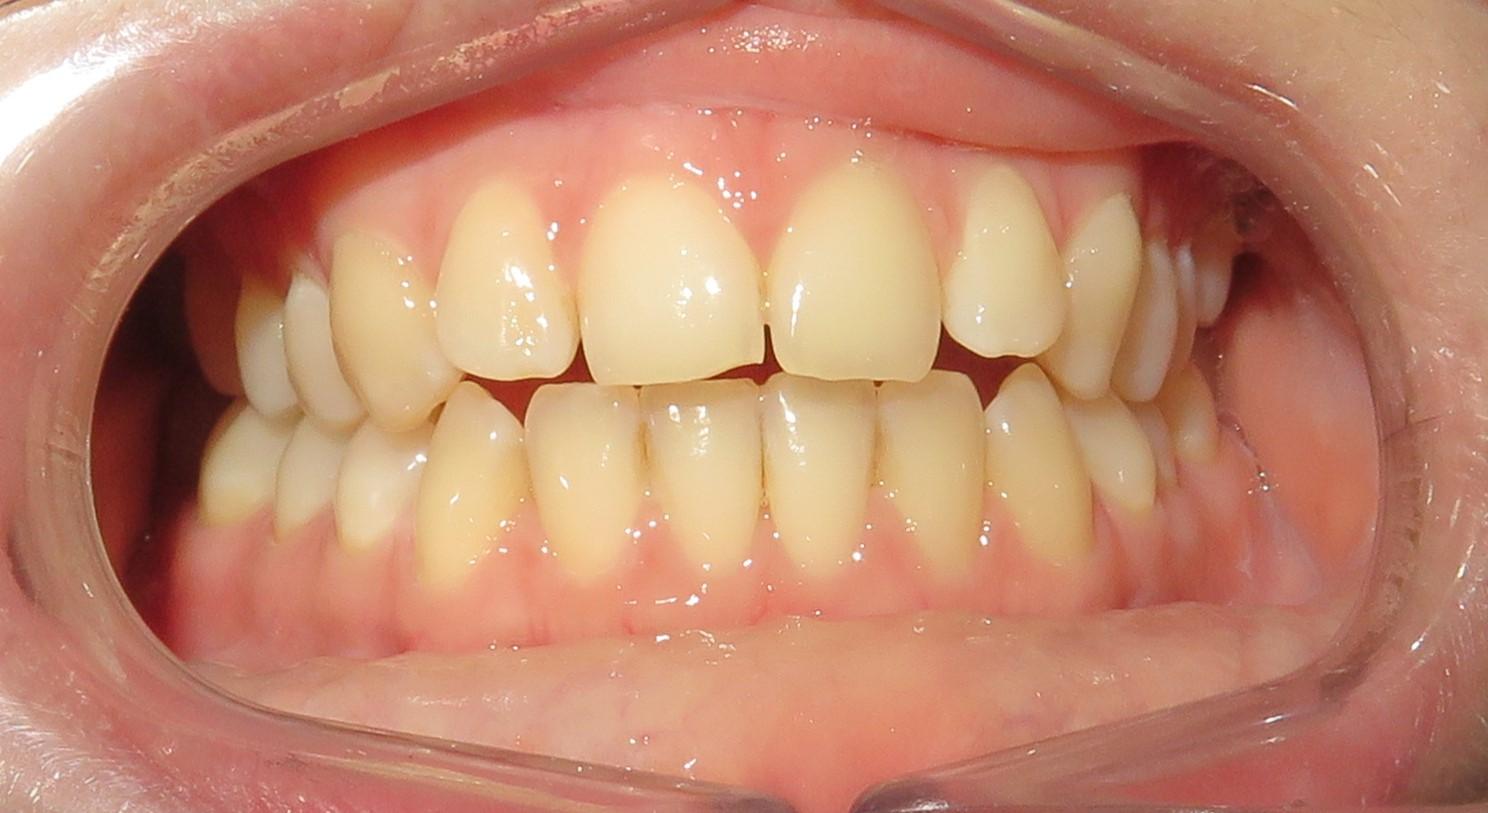

Leczenie aparatem stałym metalowym ligaturowym, które trwało 1,5 roku.

Głównym problemem był zgryz otwarty przedni, a także rotacje zębów oraz mała ekspozycja siekaczy w uśmiechu.